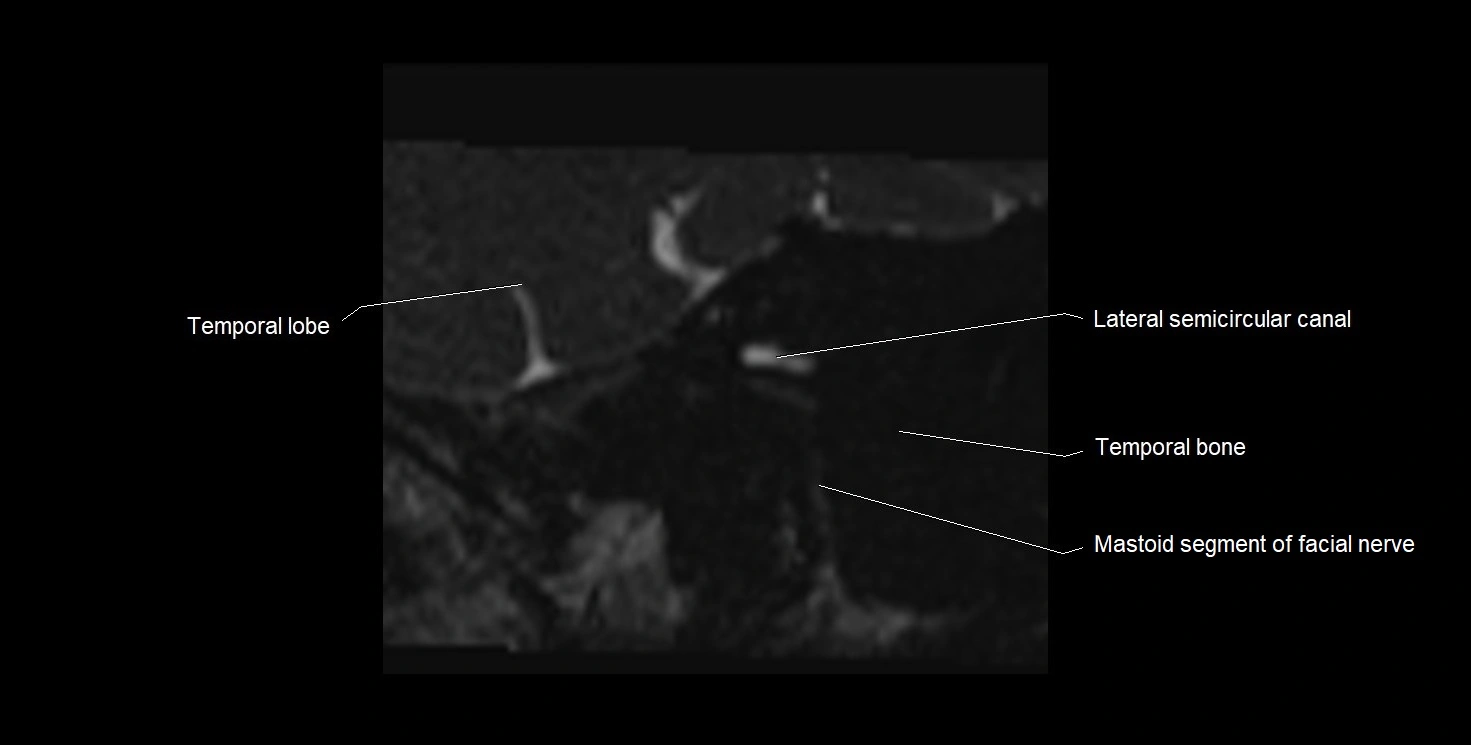

MRI images

image